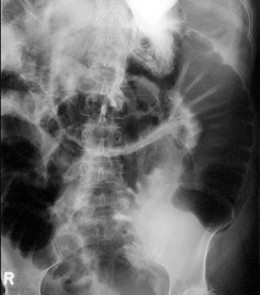

Всички болни, при които има съмнение за чревна непроходимост трябва да бъдат консултирани с хирург. Уточняването на диагнозата става след подробен преглед на болния и задължително рентгеново изследване на корема.

Началото на заболяването при дебелочревна непроходимост, особено при туморни заболявания е постепенно, с напредващо подуване на корема, понякога до големи размери, спира отделянето на газове и изпражнения, слаби до умерени болки в епи- или хипогастриума, по-късно започва повръщане на чревно съдържимо. При заклещване на херния или усукване на чревна бримка заболяването протича по-бурно.

Характерен, насочващ симптом при рак, локализиран в дясната половина на дебелото черво е анемията. Не е за пренебрегване и органомегалията, установена при физикалното изследване, като насочваща (могат да се опипат различни тумори или да се установи прераздуто дебело черво). Наличието на белези от предходни операции също е насочващо за наличие на вътрекоремни сраствания и съответно причинен от това илеус.